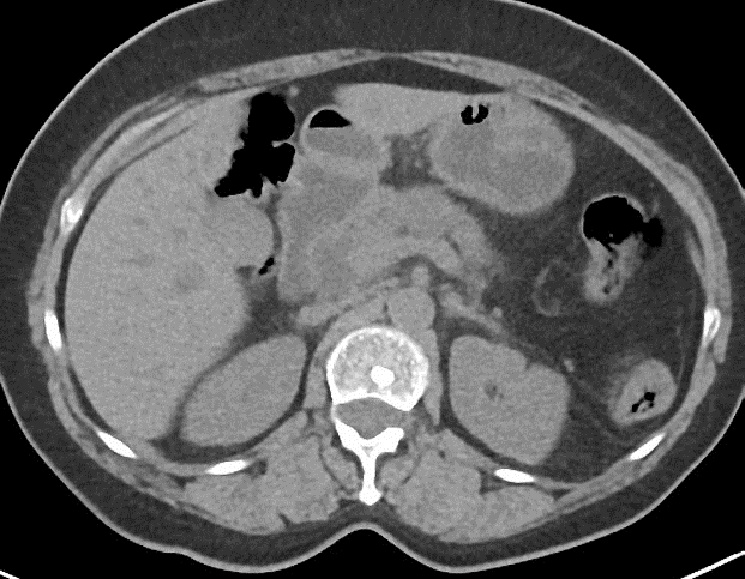

Les

metastases du pancreas : Les

metastases pancreatiques sont rare et le plus souvant

viennent de tumeurs renales ,

pulmonaires, mammaires, colo-rectales et le mélanome . Les

metastases du pancreas souvent sous forme de masse ( 50-75%

), difusant ( 5-45% )et multiple nodulaire ( 5-15% ) ,

Image echographique est un masse ou nodule hypoechogene

situe peripherique parenchymateuse du pancreas . Image

radiologique TDM le plus souvent est aspect de masse ,

nodule

hypodense parfois isodense , unique ou multiple se presente

dans le parenchyme du pancreas , situe souvent peripherique et rarement s'accompagne de etat de

compressible des conduits pancreatiques . Les metastases de

tumeur renal souvent se donne de image hypervascularise et

necrose central apres injection de contrast intraveineuse .